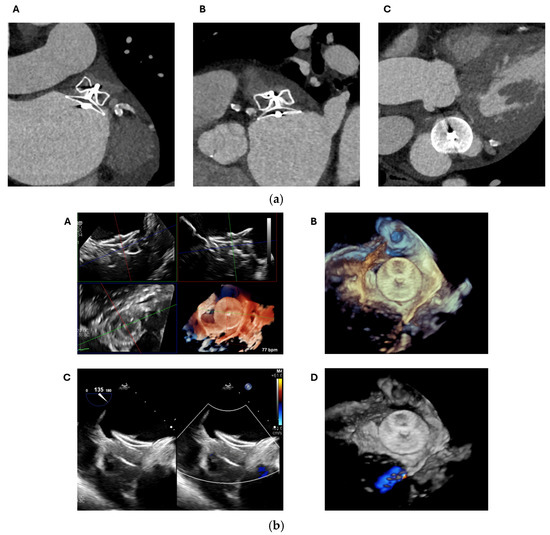

2.1. Cardiac CT

2.1.1. Anatomical Contraindications

2.1.2. LAA Measurements

2.1.3. Assessment of the Inter-Atrial Septum

2.1.4. Other Anatomical Considerations